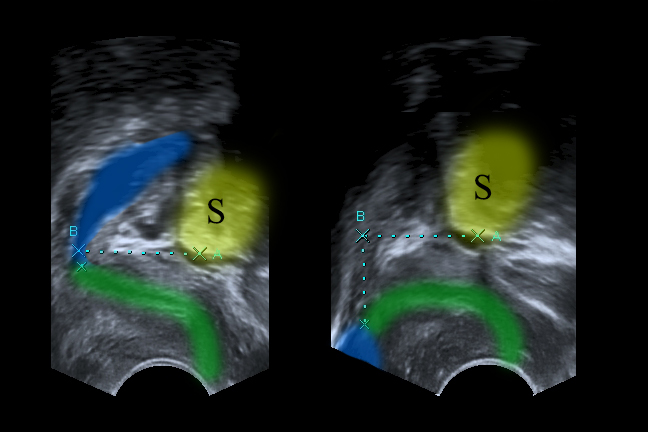

A 62-year old patient presented with second degree pelvic organ prolapse. Other than the typical symptoms of significant bladder and uterine descent, she denied being incontinent. The urodynamic studies confirmed this finding and the urethral closure pressure was normal. Interestingly the cough-test after reposition of the prolapse was positive. After thorough explaining of occult urinary incontinence, the patient still wished a two-step approach.

Want to read more about how to depict stress urinary incontinence in ultrasound? Check this article.